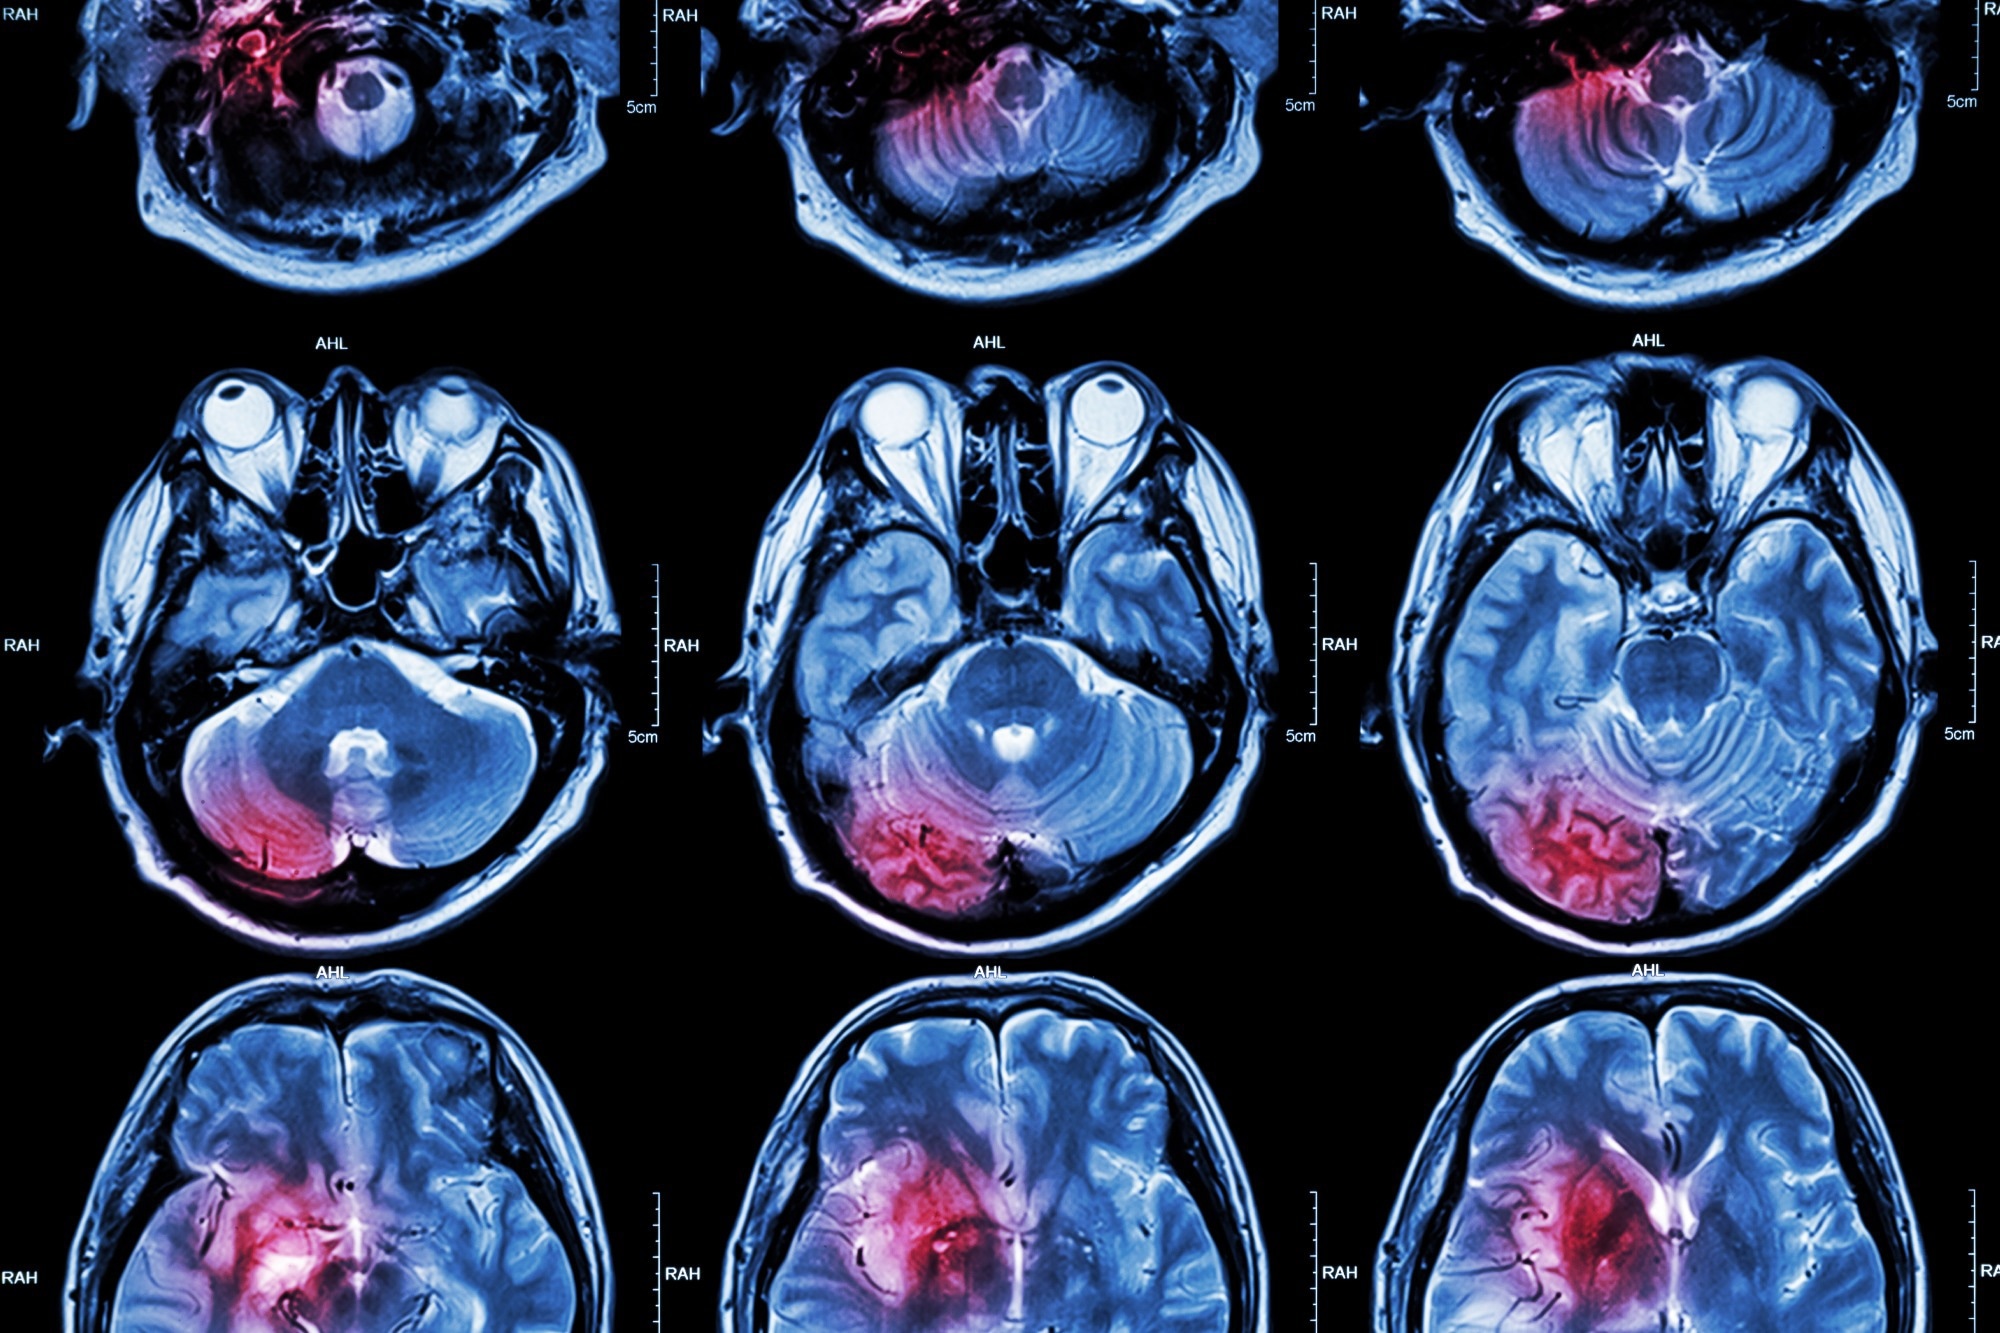

Study: The third Intensive Care Bundle with Blood Pressure Reduction in Acute Cerebral Haemorrhage Trial (INTERACT3): an international, stepped wedge cluster randomised controlled trial. Image Credit: PuwadolJaturawutthichai/Shutterstock.comStudy: The third Intensive Care Bundle with Blood Pressure Reduction in Acute Cerebral Haemorrhage Trial (INTERACT3): an international, stepped wedge cluster randomised controlled trial. Image Credit: PuwadolJaturawutthichai/Shutterstock.com

Intracerebral hemorrhage is a type of stroke that is untreatable and accounts for ~20% of the 20 million stroke cases occurring worldwide every year, mostly in LMICs.